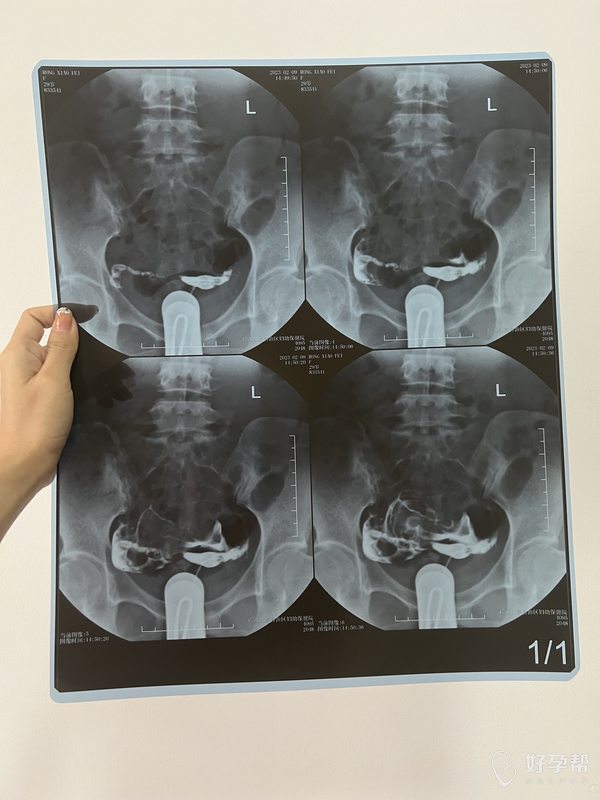

输卵管是否通畅为什么还怀不上

亲爱的,输卵管通畅只是代表卵子和精子能相见,是自然怀孕的基础,但是输卵管通畅不是万能的,影响怀孕因素有很多,比如说:卵子、精子质量如何?输卵管腔内纤毛摆动功能和输卵管蠕动功能如何?宫腔是否有长有赘生物?宫腔是否粘连?宫腔内膜是否正常?还有精神心理因素、免疫因素等等。建议自然备孕半年,若不怀孕建议就诊正规专科医院进行医学指导妊娠。